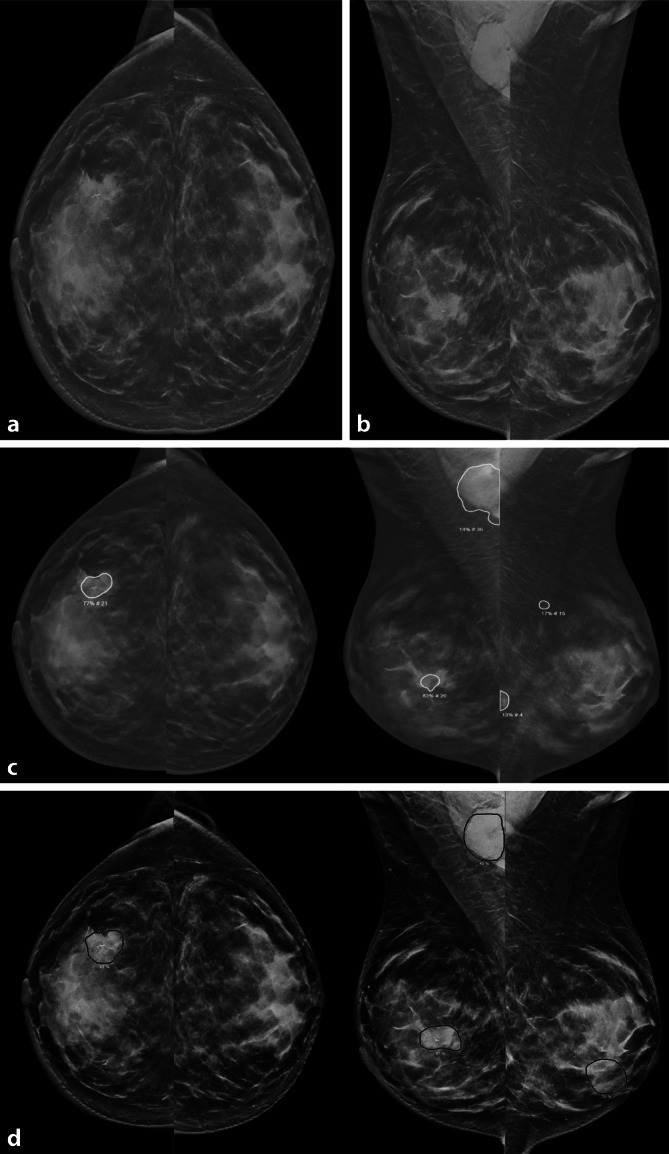

Standard radiological methods: In principle, AI applications are available for all imaging modalities, with a particular focus on mammography in breast diagnostics.

Methodical innovations: AI promises to filter examinations into negative and clearly positive findings, and thereby reduces part of the radiological workload. Other applications are not yet as widely established.

Performance: AI methods for mammography, and to a lesser extent tomosynthesis, have already reached the diagnostic quality of radiologists.